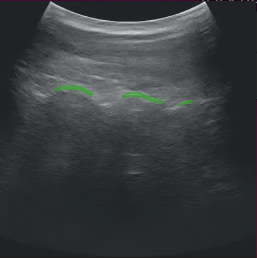

This section describes the details of the ultrasound segmentation sample application as well as how to load a custom inference model into the application for some limited customization. Out of the box, the ultrasound segmentation application comes as a “video replayer” and “AJA source”, where the user can replay a pre-recorded ultrasound video file included in the runtime container or stream data from an AJA capture device directly through the GPU respectively.

This application performs an automatic segmentation of the spine from a trained AI model for the purpose of scoliosis visualization and measurement.

Fig. 12 Spine segmentation of ultrasound data

and outputs a semantic segmentation of the same size with two channels representing bone contours with hyperechoic lines (foreground) and hyperechoic acoustic shadow (background).